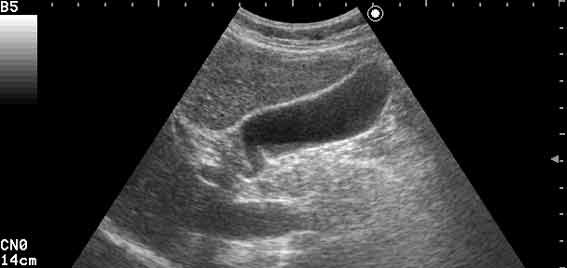

УЗИ: нормальный желчный пузырь

Норма

Tags: sonography, gallbladder, normal